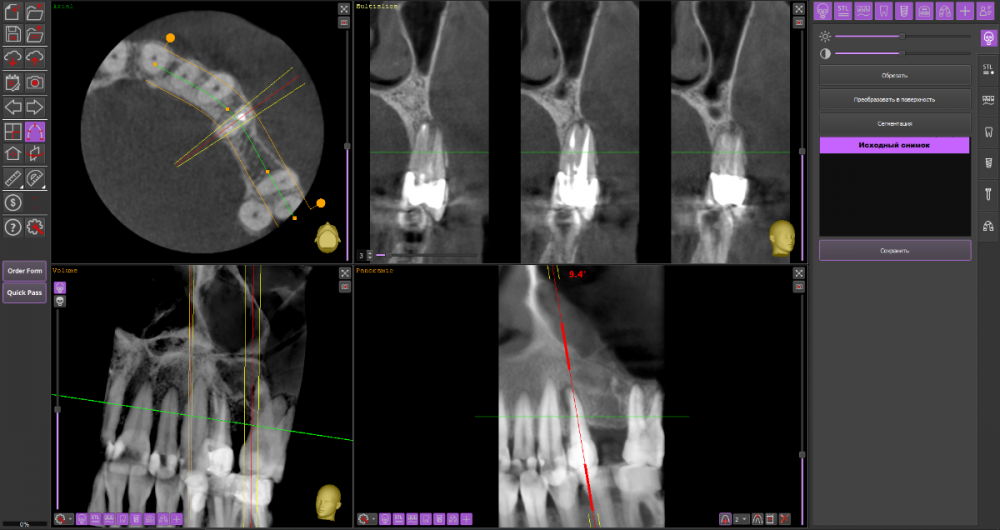

Ulitka Опубликовано 24 января, 2024 Поделиться Опубликовано 24 января, 2024 Добрый день. Уточните, пожалуйста, можно ли спасти зуб 24? Дня 4 назад появилась болезненность при надкусывании, сейчас боли нет ,но есть небольшая припухлость в области корня зуба. Один стоматолог сказал без 3Д снимка, что можно попробовать пролечить и заново протезировать. Второй по 3Д говорит, что у корня зуба нет частично кости, необходимо удалить зуб, чтобы прошло воспаление и кость восстановилась, далее имплантация. Прилагаю КТ https://drive.google.com/file/d/1xQxirzscf1404qjDOck7pBpt04szT7sa/view?usp=drive_link Ссылка на комментарий

wladdX Опубликовано 25 января, 2024 Поделиться Опубликовано 25 января, 2024 Пара скриншотов 1 Ссылка на комментарий

Carioznik Опубликовано 26 января, 2024 Поделиться Опубликовано 26 января, 2024 (изменено) Чую я, зуб не простой. Ищите эндодондиста для лечения этого зуба , имхо, без микроскопа в этом зубе делать нечего. Но и при лечении с микроскопом - будьте готовы, что в процессе могут быть найдены в зубе "сюрпризы" и его, всё -таки, придется удалить. Либо, вероятный процент успеха, несмотря на проведенное лечение, все равно, у этого зуба, будет снижен. Чтобы, более-менее, разобраться одного КТ мало. Нужен осмотр Изменено 26 января, 2024 пользователем Carioznik 1 Ссылка на комментарий